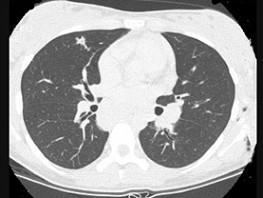

问题 7岁,男,发热、消瘦,数月前触及颈部淋巴结肿大,CT和MR检查如图,请选择最可能的诊断 ( )

选项 A、转移性淋巴肿大 B、胸腺瘤 C、结节病 D、淋巴结核 E、淋巴瘤

答案 E